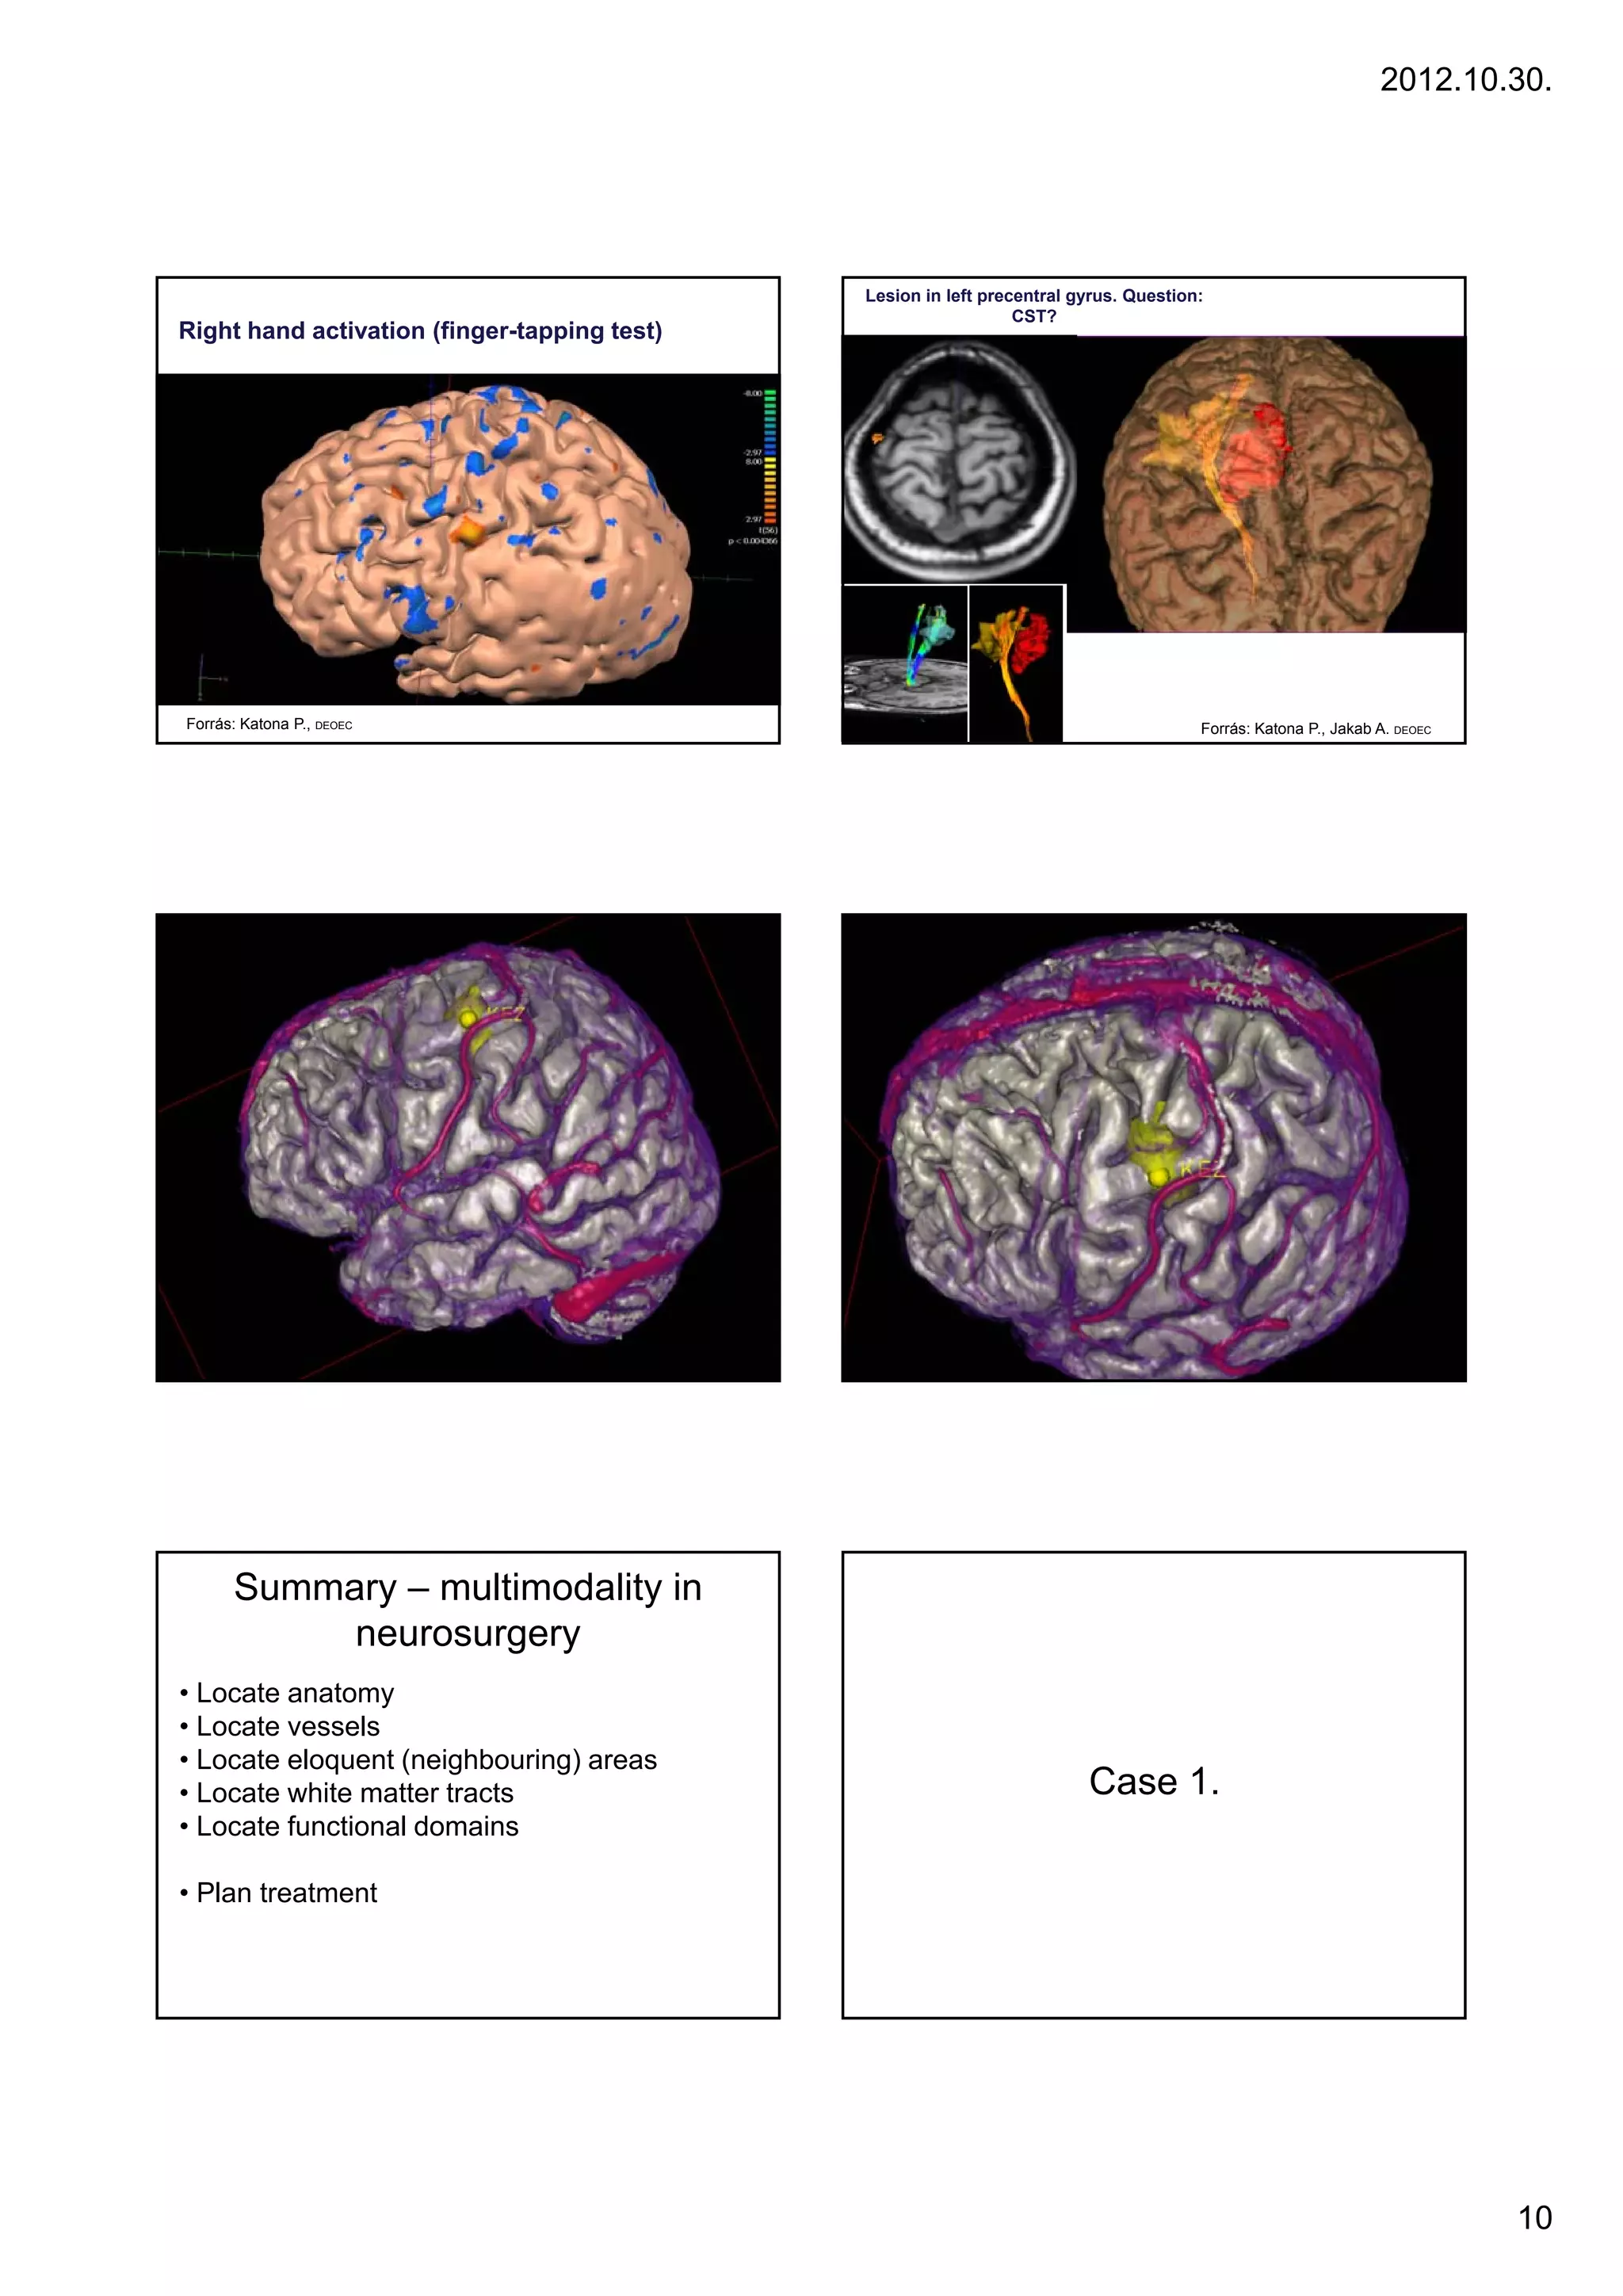

Lesion in left precentral gyrus. Question:

CST?

Right hand activation (finger-tapping test)

Forrás: Katona P., DEOEC                                                               Forrás: Katona P., Jakab A. DEOEC